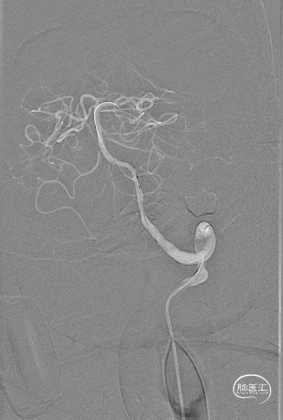

外院DSA(2023.02.09):左侧椎动脉V4段重度狭窄,右侧椎动脉V3段远端闭塞。前循环未见明显异常。